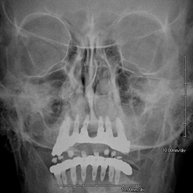

- RX Ortopantomografía (RX Panorámica dental)

Técnica mediante la cual, utilizando rayos X, se obtienen imágenes de ambos maxilares y de las piezas dentarias para su estudio. Indicaciones: piezas dentales retenidas, estudio de ortodoncia, estudio de implantes dentales.